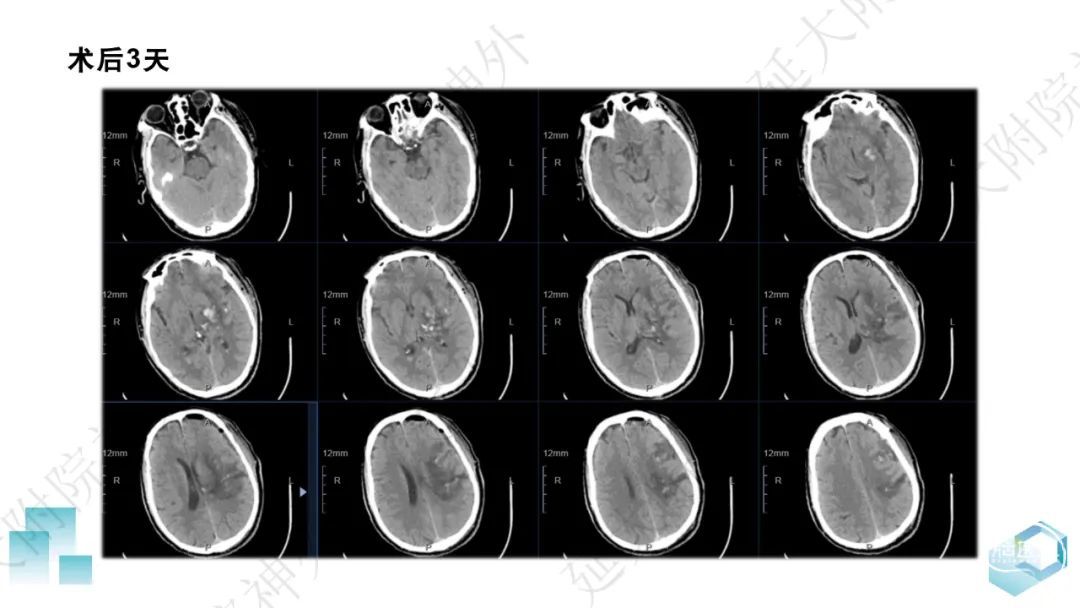

今天为大家分享的是《监测有道丨颅脑创伤-神经重症周刊》第332期,由延安大学附属医院神经外科贾云峰主任医师带来的:左侧基底节区出血破入脑室一例神经内镜下血肿清除术,欢迎阅读、分享。